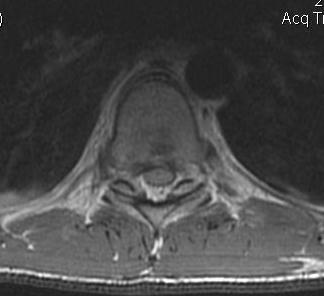

MRI

- HNP

- cord signal change

- assess posterior ligament integrity

- assess level of conus medullaris

- MRI to exclude disc / determine level of conus

- consider anterior approach if HNP / above level conus